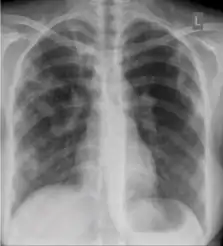

These are films that are completely normal, with no identifiable cardiothoracic or musculoskeletal abnormality.